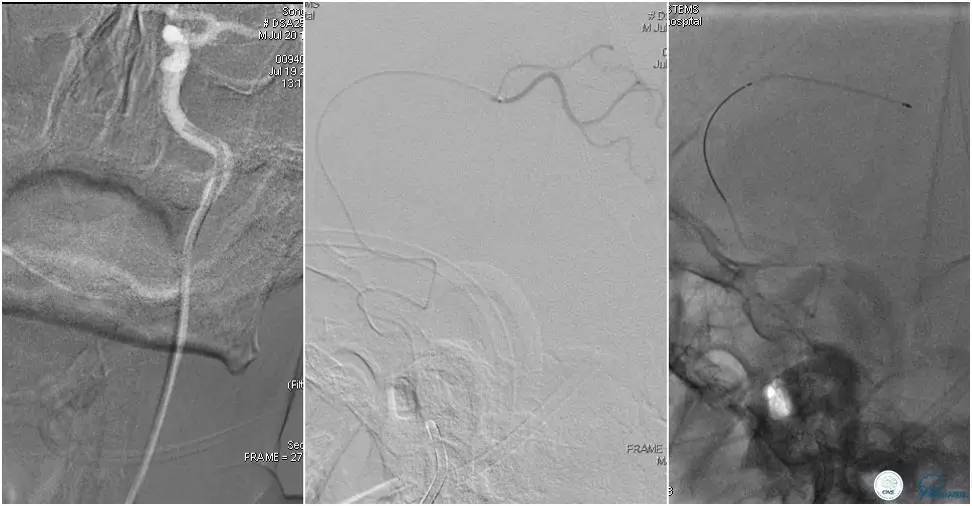

12:35穿刺成功,TOT 185min。3型主动脉弓,右侧颈内动脉起始部狭窄70%,右侧大脑前动脉A1段未显影。

双侧大脑前动脉A4段闭塞,右侧大脑前动脉由左侧大脑前动脉经前交通动脉代偿供血。

6F Envoy置于颈内动脉C3段,选用Solitaire-FR 4*20mm支架释放于右侧大脑前动脉,完全覆盖血栓。

6F Envoy置于左侧颈内动脉C3段,选用Solitaire-FR 4*20mm支架释放于右侧大脑前动脉取栓1次,血流达TICI 2b。

Solitaire-FR 4*20mm支架释放于左侧大脑前动脉取栓1次,取出少许血栓重复造影左侧大脑前动脉胼周动脉开口后,右侧大脑前动脉A2段以远未显影,考虑栓子逃逸。

选用Solitaire-FR 4*20mm支架分别于右侧大脑前动脉A2-A3段,左侧胼周动脉,右侧胼周动脉取栓3次。

双侧大脑前动脉完全显影,TICI 3级,TOR 261min。